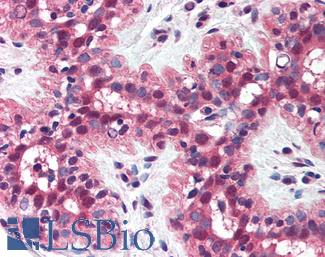

AMACR

CDKN1B